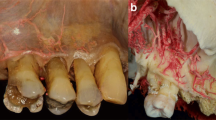

Major- and secondary branches of the GPA and its relation to the palatine spine, different anastomoses with NPA and LPA as well as with contralateral branches of the GPA were recorded (Figs. 1 and 2). Another important record of patients with an edentulous upper jaw revealed that due to the resorption of the bone, the GPA developed a curvy pathway especially at the area of the molars-premolars (Fig. 3). Also, some penetrating intraosseous branches at the premolar-canine area were observed (Fig. 4). The blood supply around the maxillary tuberosity was also presented. As soon as the greater palatine artery emerges out from the greater palatine foramen, it sends one to two branches toward the tuberosity and also the lesser palatine artery sends one to two branches forming anastomoses at this area (Fig. 5). The abovementioned findings are summarized in Fig. 6, which clearly demonstrates the complexity of palatal blood supply.

Curvy pathway of the greater palatine artery (GPA) in the edentulous areas shown by latex milk injection. a Bilateral view showing curvy pathway of the GPA as well as horizontal shrinkage of the alveolar ridge due to atrophy at an edentulous site. b Normal straight pathway of the GPA. c Curvy pathway of the GPA at the area of the missing upper left molars. d Excessively altered pathway of the GPA in a totally edentulous specimen. e Curvy pathway of the GPA in the upper right premolar area

Within the present study, we were able to present comprehensive novel results related to palatal blood supply, which can be integrated into clinical practice when planning and executing palatal surgical interventions. Information available in anatomical literature and textbooks are lacking clinically focused details of the palatal vascular network (intraosseous branches, various anastomoses, which would affect the injection of local anesthetics and incision design; changes in the course of vascular pathways due to loss of dentition and bone resorption). Our study provides a solid anatomical basis on local characteristics of the hard palate and maxillary tuberosity for clinicians who are interested in surgical interventions of the posterior maxilla, such as connective tissue grafting, removal of impacted canines, implant placement, and sinus floor elevation. We demonstrated arterial anastomoses between contralateral and ipsilateral vessels of the palate (Figs. 1 and 2) along with additional vascular mapping of the maxillary tuberosity (Fig. 5). The application of corrosion casting and latex milk injection following Thiel’s fixation simultaneously allowed for blood vessel mapping together with localization of arteries within the palatal mucosa relative to already identified anatomical landmarks. This unique combination of different staining methods has enabled us to demonstrate new types of anastomoses between GPA, NPA, and LPA, or previously unknown intraosseous branches of GPA, alteration of GPA pathway in edentulous sites and tuberal blood supply. Corrosion casting is a widely recognized method in literature for three-dimensional visualization of vascular structures [28]. In the present study, this approach was successfully applied to investigate possible previously unknown pathways of the GPA and its subbranches. Moreover, according to our knowledge, we were the first to utilize latex milk injection [27] to visualize the topographical relation of the GPA branches and subbranches to adjacent tissues within the palatal masticatory mucosa. The palatal mucosa is the most frequently used donor site for connective tissue graft harvesting [8]. Nevertheless, there is only scarce data on the palatal anastomoses possibly influencing intraoperative bleeding and postoperative blood supply of palatal donor sites. SCTGs are usually harvested from an area between the canine and the second molar of the palate by leading a horizontal incision and then the tissue is harvested by either the trapdoor technique [11] or the single incision approach [6]. These approaches, depending on the number, direction, and depth of incisions might afflict a certain risk for arterial damage and a compromised postoperative blood supply. According to our results, several cases of contra- and ipsilateral anastomoses between GPA, NPA, and LPA were demonstrated in the cadavers studied. This might provide an anatomical basis for physiological experiments investigating whether additional submucosal deposition of local anesthetics to contralateral major palatal foramen and/or nasopalatine foramen might be necessary to reduce intraoperative bleeding during palatal surgeries, e.g., SCTG harvesting and sinus floor elevation. Moreover, based on the presence of newly found contralateral anastomoses, we think that in surgeries concerning the palate, also contralateral blood circulation might be affected. Therefore, bilateral connective tissue harvesting may lead to impaired postoperative blood supply and flap necrosis. We too successfully demonstrated the existence of the so far not well-documented intraosseous GPA branches of palatal arteries (Fig. 4). A similar anatomical relation is known in the lower jaw, where nutritive subbranches of the sublingual arteries penetrate the lingual cortical layer of the mandible [31, 32]. Based on anatomical and clinical experiences with lingual intraosseous arteries [32], their palatal counterparts might be responsible for the nutrition of the maxilla and possibly the Schneiderian membrane. Nevertheless, due to their small diameter, they do not pose a significant risk for profuse intraoperative bleeding when compared to lingual nutritive branches. The distribution of the palatal intraosseous branches showed a pattern running parallel to the pathway of GPA.

A study by Reiser et al. [20] suggested that the greater palatine neurovascular bundle lies 17 mm from the gingival margin in patients with high palatal vault, and 12 mm from the gingival margin in patients with medium palatal vault, while in patients with low palatal vault the distance was 7 mm. According to our present findings, in edentulous cadavers due to the resorption of the alveolar ridge, the area for the pathway of the GPA might decrease in apico-coronal and oro-vestibular dimension and the GPA would exhibit a more undulating pathway. We were able to demonstrate that in edentulous cases the GPA with its subbranches became more superficial, which might increase the risk of GPA injury during any type of palatal flap preparation, e.g., connective tissue graft harvesting or during augmentation procedures. Due to this specific curvy outline of arteries, the distance of the GPA from the crest was reduced by 3–4 mm, thus increasing the risk for arterial injury during connective tissue harvesting. Therefore, at edentulous sites, superficial removal of a FGG can be a more secure clinical procedure for connective tissue harvesting as opposed to the single incision or trapdoor techniques.